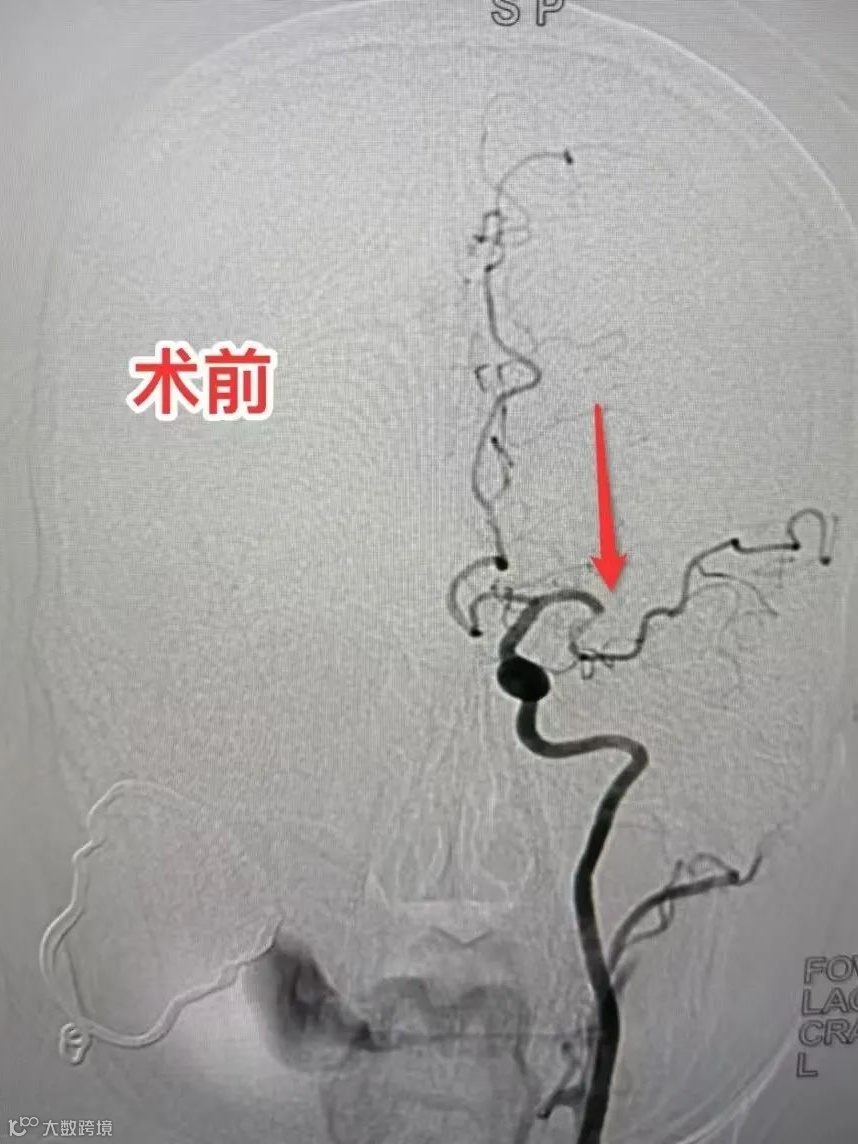

神经内科副主任陈祥峰认为,该患者初步诊断为急性脑栓塞(TOAST:心源性栓塞型)合并其他病症,患者有溶栓禁忌症,但有经皮颅内动脉取栓手术指征,经与家属详细沟通签字同意后团队立即展开手术救治。

当天晚上,在急诊科、介入室、麻醉科的快速的紧密配合下以最快的速度送介入室给予经皮颅内动脉取栓手术治疗,术中顺利开通左侧大脑中动脉闭塞处,术中取出约1.5CM长度的血栓。